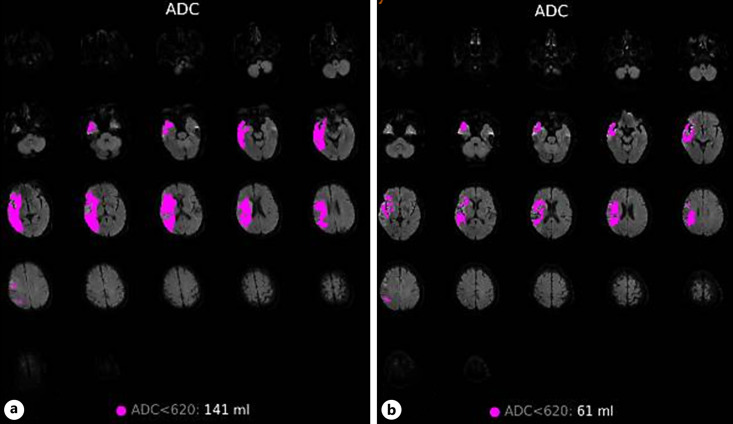

Case presentation: A 58-year-old male presented with a generalized tonic-clonic seizure. Emergent magnetic resonance imaging (MRI) revealed an extremely large infarction lesion in the right hemisphere with an Alberta Stroke Program Early Computed Tomographic Score (ASPECTS) value of 2 and occlusion of the terminal right internal carotid artery. The patient was immediately transferred to the Digital Subtraction Angiography (DSA) Unit for endovascular treatment with a stent retriever. After a rapid successful reperfusion with expanded treatment in cerebral infarction (eTICI) score of 3, the patient promptly recovered 24 h after the procedure. A brain MRI was repeated after 8 days of admission, and interestingly, the DWI lesion showed significant reversal. The modified Rankin scale (mRS) at discharge was 2 and 1 at 90-day follow-up, respectively.